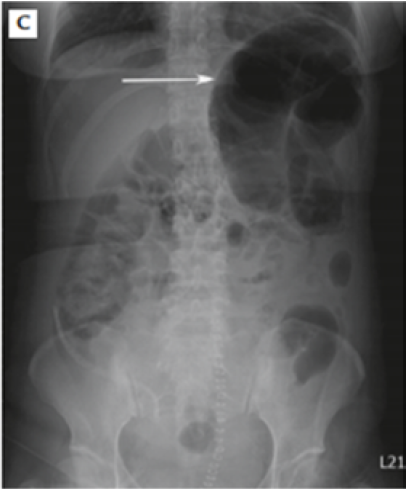

Figure 3: Colonic Gaseous Dilatation